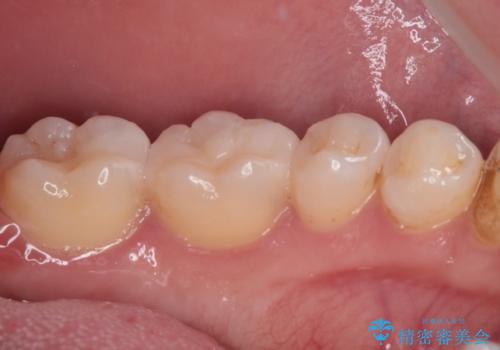

精密な型取りと、ラバーダム防湿下での接着操作により、歯と詰め物の隙間を最小限にとどめることができ、処置後はしみる症状が一切なくなりました。